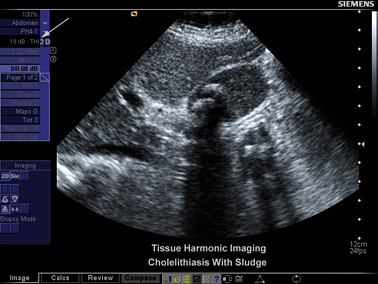

Bei der Untersuchung der Galle, z.B. bei Verdacht auf Gallensteine, führen wir als erstes stets eine Ultraschalluntersuchung durch. Gallensteine, Grieß (kleinste Steine) und Schlamm (Sludge = stark eingedickte Gallenflüssigkeit) sind hier als Schatten erkennbar.

Aufgestaute erweiterte Gallenwege und eine Veränderung der Gallenblasenwand zeichnen sich ab. Die Untersuchung ist schnell, ungefährlich und belastet nicht.

Gallenblasenstein 2

(Zum Vergrößern bitte anklicken)